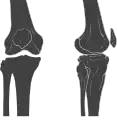

![]() Human knees | |

![]() Right knee (front-right view) | |